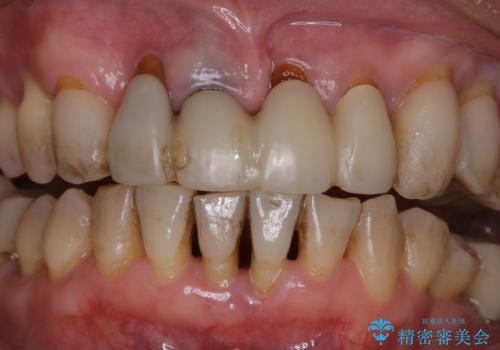

- 定期的にメンテナンスにいらしている方です。特にお変わりないとのことでPMTC60分コースで全体的なクリーニングを行いました。